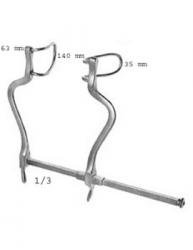

Ecarteur CHARNLEY complet

L’écarteur Charnley est proposé sous forme de set complet

Notre écarteur charnley est fabriqué en Allemagne

il est garanti 5 ans contre un défaut de fabrication